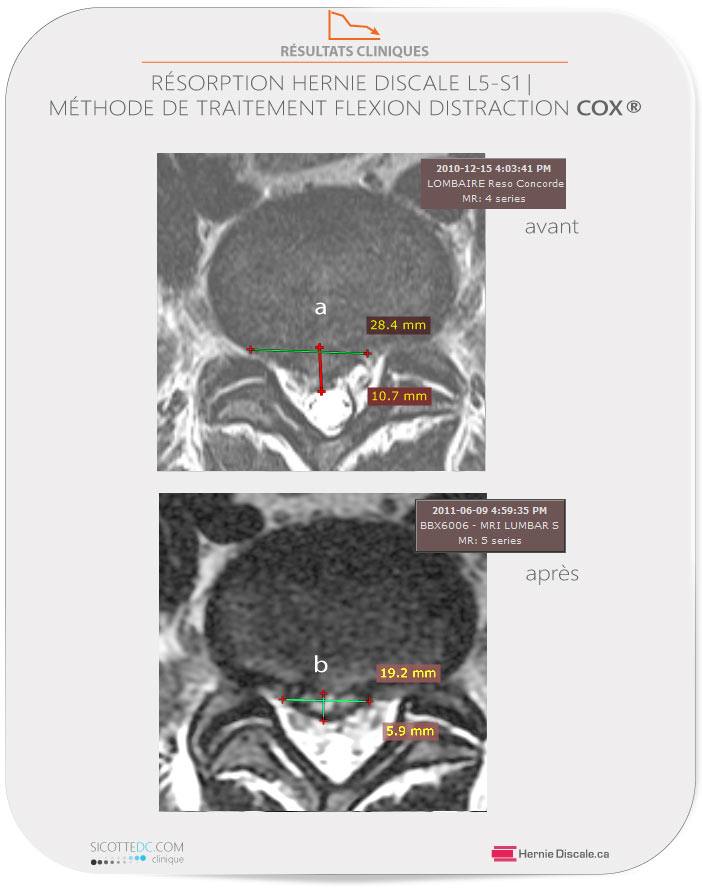

RÉSORPTION D’UNE HERNIE DISCALE AVEC TRAITEMENT MÉTHODE COX®

b: Trois mois après le dernier soin de distraction Cox®, la lésion a subi une résorption pour atteindre 19,2 mm x 5,9 mm. Une diminution de volume, sur le plan axial, de 62.7%.

Référé à notre clinique par sa conjointe il avait été examiné par d’autres cliniciens qui n’ont toutefois pas perçu les signes de lésion discale. Le patient était antalgique (posture modifiée en raison de la douleur) et avait une douleur située à 7/10. L’examen physique démontre la suspicion d’une sciatalgie (fort probablement à cause d’une hernie discale). Une IRM est prescrite et vingt-quatre heures plus tard, le patient revient à notre clinique pour débuter ses soins. Après 12 semaines de soins continus, le patient retrouve une vie normale.